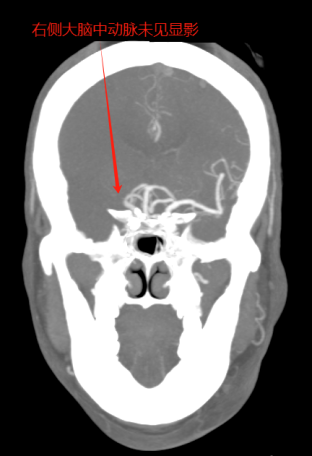

卒中中心值班医师(绿道医师)马上给予指示:收费处绿色通道挂号,院前医师车上完成血液抽取、血糖及心电图检查,并将患者绕行急诊紧急送往CT室进行头颅CT检查。患者心电图显示I、AVL、V5、V6导联ST段明显改变,考虑同时合并急性冠脉综合征,患者存在急性心梗的可能。随即加查肌钙蛋白,同时送检头颅CT平扫+CTA检查。CT检查结果明确了患者右侧大脑中动脉的M1段闭塞,确诊为急性脑梗死。肌钙蛋白检测结果亦回报:12.83ug/ml,结合心电图的表现,确诊为急性非ST段抬高型心肌梗死。

头颈CTA示右侧大脑中动脉起始处闭塞